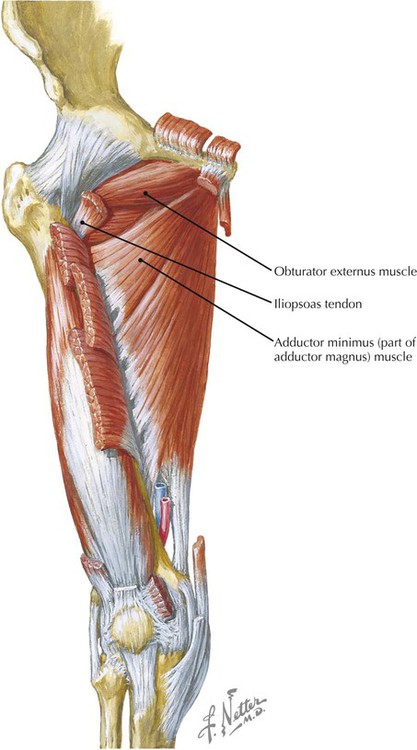

Анатомия и Функции Мышцы Adductor Magnus